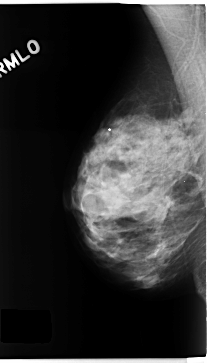

C_0272_1.RIGHT_MLO

RIGHT_MLO LINES 4712 PIXELS_PER_LINE 2688 BITS_PER_PIXEL 12 RESOLUTION 50 NON_OVERLAY